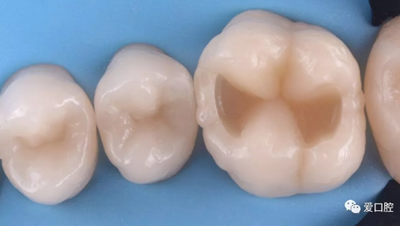

六、 充填體折斷或脫落

腐質(zhì)去除不干凈,充填體與牙本質(zhì)、牙釉質(zhì)未形成有效粘接。粘接時隔濕不良,血液或唾液污染創(chuàng)面,造成粘接失敗。窩洞設(shè)計缺陷。如 PPT20 圖示在直接承力的位置,較薄的充填體的邊緣容易受力發(fā)生折斷。 凹形斜面保證了充填體的邊緣厚度從而增加了抗力 。

處理方法:重新充填。